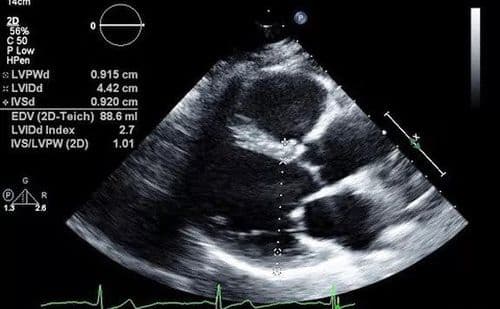

हा धोका टाळण्यासाठी बरं झाल्यानंतर हृदयविकारतज्ञांचा सल्ला घ्या. त्यांच्या सल्ल्याने ईसीजी, टू डी इको यासारख्या चाचण्या करून घ्या. विशेषतः छातीत दुखणं, धाप लागणं अशी लक्षणं असतील तर हे करणं गरजेचं आहे.